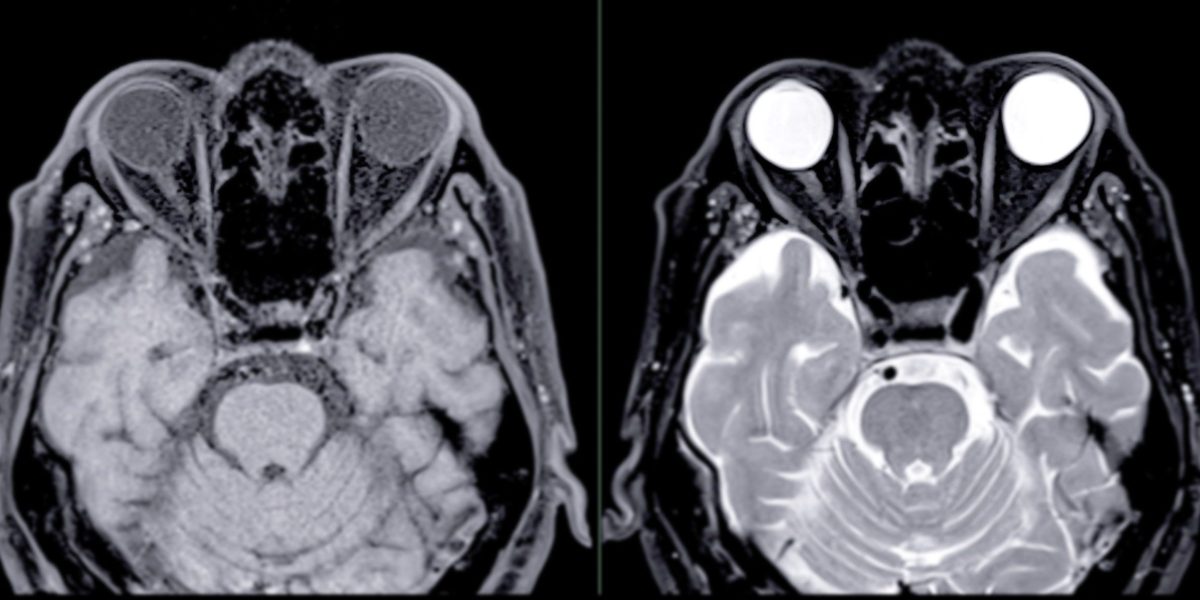

大腦灰白質

✔ 灰質+白質一起退化 → 形成失智症

灰質負責內容、白質負責傳遞。當兩者同時退化,就會出現典型認知功能障礙的記憶、語言、情緒與生活功能下降。

✔ 灰質: 負責記憶、判斷與情緒的大腦核心

灰質是大腦處理資訊的「主控台」。

✔ 白質:負責大腦訊號傳遞的訊號高速公路

白質就像大腦裡的「訊號高速公路」,讓不同腦區能快速交換訊息。